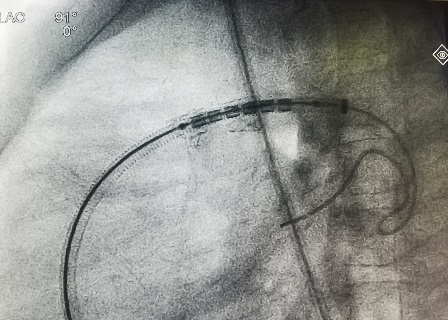

在导丝引导下,右心导管通过断裂的支架,到达左肺动脉远端。再沿导丝送入Pul-Stent,和球囊载体,覆盖断裂的支架。

术中植入Pul-stent S20支架(EV3 10-3和12-3球囊)